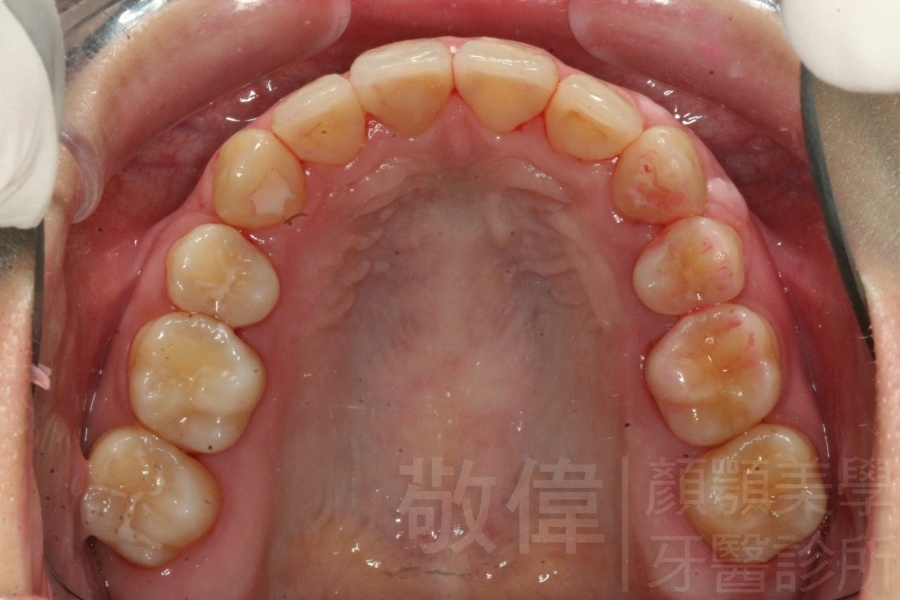

齒顏矯正/上顎暴牙且牙齒極度混亂

矯正前-右   矯正前-正   矯正前-左

矯正後-右   矯正後-正   矯正後-左

矯正前-上   矯正前-下

矯正後-上   矯正後-下

<個案說明>

上顎暴牙且牙齒極度混亂,經由矯正之後,臉型大幅度改善,牙齒的排列更加的整齊健康。相較於之前眼神充滿精神,自信心展現無遺。